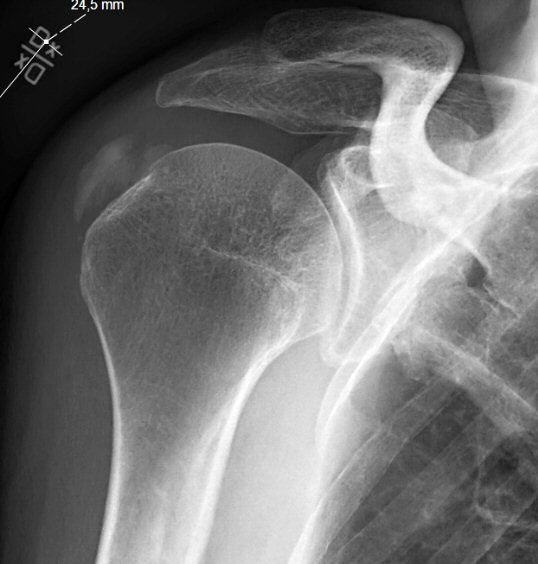

- Röntgenbild med typisk förkalkning i supraspinatussenan

Två exempel på kalkaxlar, både med kraftig smärta och förhöjt CRP men återställda efter några dagar.